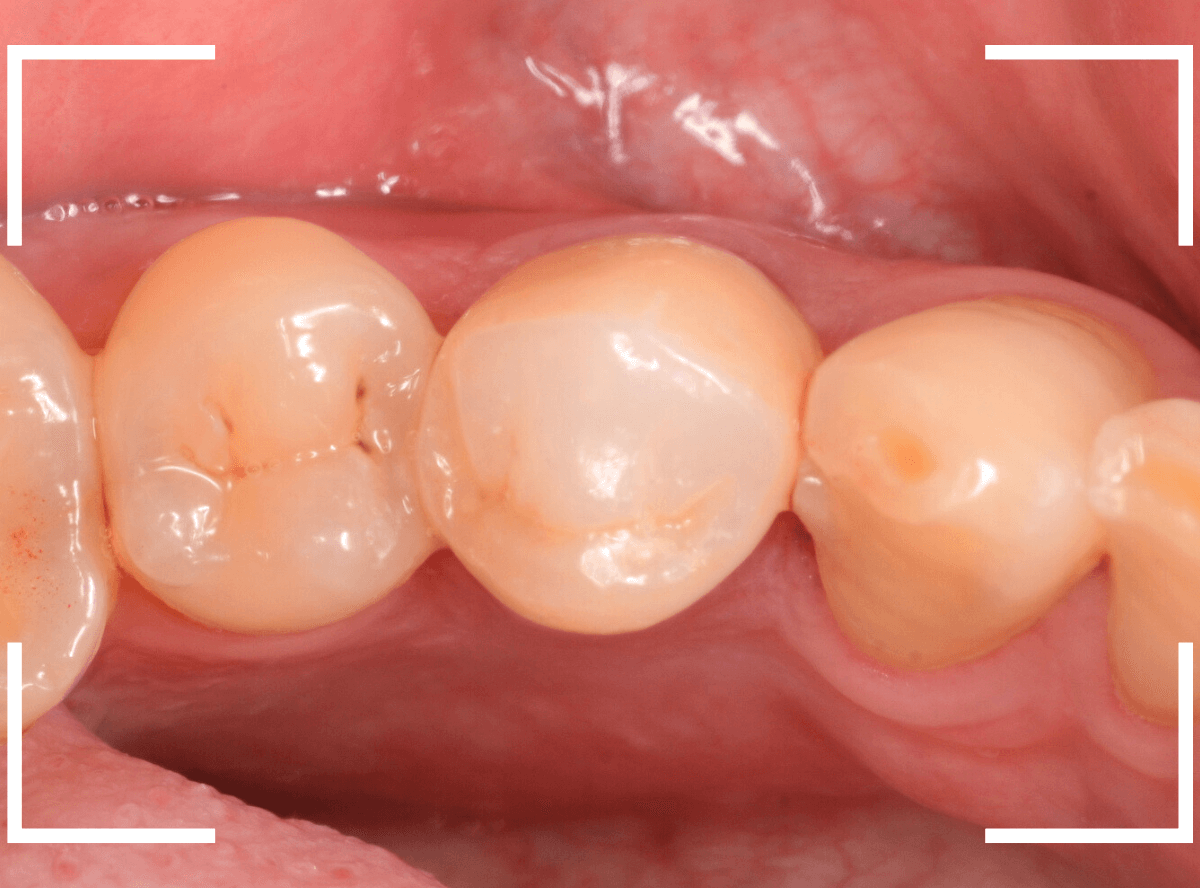

set後の写真になります。

お口の状態に、問題なく合わせられたかと思います。